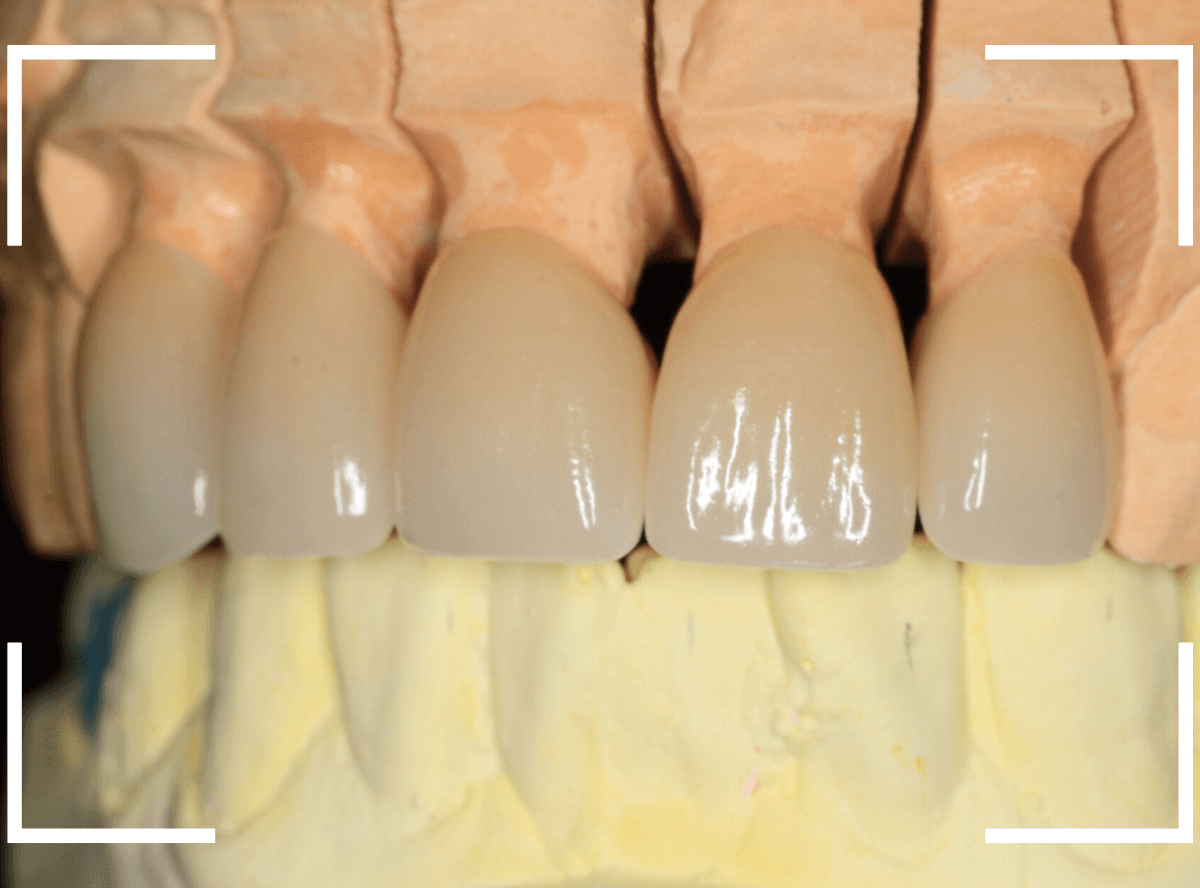

模型上で精密に制作します。

今回のように、本数が多い時、精密性が求められる時などは、いきなり仕上げをせずに、ジルコニアのフレームにワックスを盛った状態で、お口の中に試適してフレームの適合や患者さんに歯の外形のチェックなどをしてもらいます。

試適で患者さんにも確認がとれましたので、表面をセラミックで最終仕上げをします。

模型上で精密に製作します。